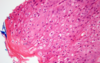

MDx

Ulcerative/Exudative dermatitis

MDx

Neutrophilic dermatitis/folliculitis